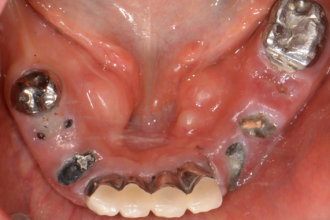

임플란트